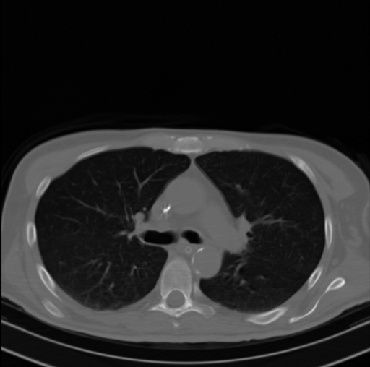

Early and reliable COVID-19 diagnosis based on chest 3-D CT scans can assist medical specialists in vital circumstances. Deep learning methodologies constitute a main approach for chest CT scan analysis and disease prediction. However, large annotated databases are necessary for developing deep learning models that are able to provide COVID-19 diagnosis across various medical environments in different countries. Due to privacy issues, publicly available COVID-19 CT datasets are highly difficult to obtain, which hinders the research and development of AI-enabled diagnosis methods of COVID-19 based on CT scans. In this paper we present the COV19-CT-DB database which is annotated for COVID-19, consisting of about 5,000 3-D CT scans, We have split the database in training, validation and test datasets. The former two datasets can be used for training and validation of machine learning models, while the latter will be used for evaluation of the developed models. We also present a deep learning approach, based on a CNN-RNN network and report its performance on the COVID19-CT-DB database.